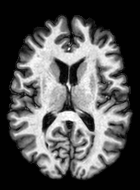

Although ISBI-61 includes longitudinal images, we performed the segmentation in a cross-sectional manner. The segmentations were generated in a similar fashion as the MS-100 dataset (Sec. 4.1) by averaging two memberships obtained using two sets of training. A typical segmentation example is shown in Fig. 7, where the subject has high lesion load (cc).